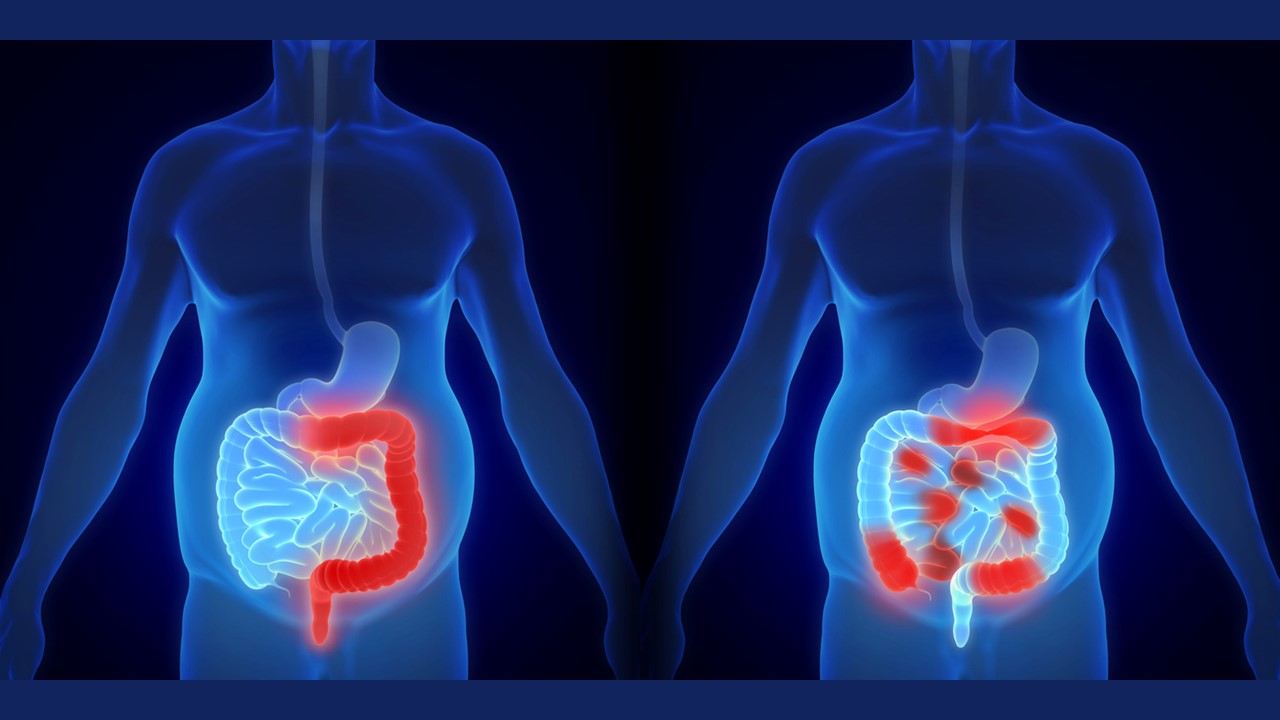

Questa approvazione amplia l’uso del farmaco a un secondo tipo importante di malattia infiammatoria intestinale (IBD), dopo il via libera per il trattamento della colite ulcerosa (UC) ottenuto nell’ottobre 2023. Mirikizumab agisce bloccando la proteina interleuchina-23p19 (IL-23p19), un elemento chiave nell’infiammazione intestinale.

L’approvazione di mirikizumab per il Crohn si basa sui risultati positivi dello studio di fase 3 VIVID-1. In questo trial, i pazienti trattati con mirikizumab hanno mostrato un significativo miglioramento rispetto a quelli trattati con placebo.